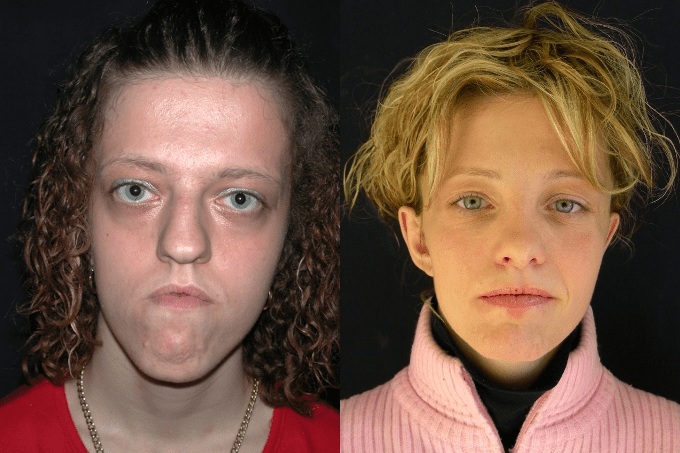

1st and 2nd STEP

Osteotomy type Le Fort III

Orthodontic treatment

Segmented Le Fort I type osteotomy

STEP 3

Rhinoplasty

genioplasty

Bitemporal lipofilling

STEP 4

otoplasty

Bitemporal lipofilling

Gingival flap

FINAL RESULTS